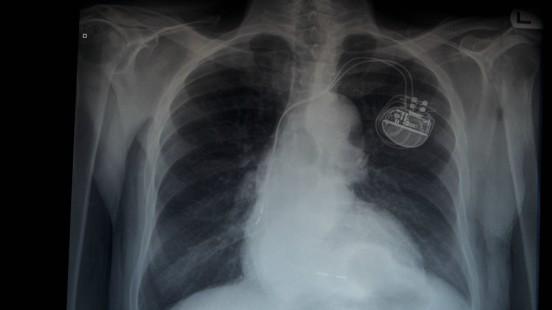

Aquest petit dispositiu, que s’implanta sota de la clavícula gràcies a una petita incisió, envia impulsos elèctrics al cor perquè pugui bategar amb un ritme constant.

El marcapassos artificial consta d’un generador d’impulsos elèctrics, el marcapassos, i un cable conductor. Per implantar-lo es fa una incisió al pit, per sota de la clavícula esquerra.

S’introdueix el cable fins a l’aurícula dreta o el ventricle dret, segons la malaltia. Si el pacient només necessita un elèctrode, es col·loca al ventricle dret. Si en necessita dos, l’altre es col·loca a l’aurícula dreta.

Es comprova que estigui ben col·locat mitjançant un procediment radiològic i, si tot està correcte, es connecta i queda sota de la pell. Després se sutura la incisió.